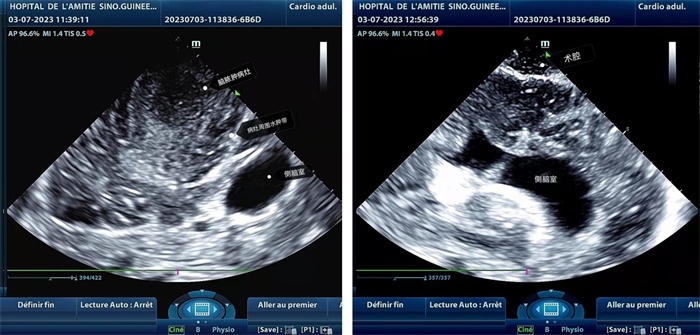

手術(shù)中,張國濱在超聲科顧秀娟的幫助下,運(yùn)用顱腦術(shù)中超聲技術(shù),通過將一次性保護(hù)套的超聲探頭置于腦組織表面,實(shí)時(shí)觀察病變的位置和形態(tài),進(jìn)一步確認(rèn)最佳手術(shù)路徑。術(shù)中超聲顯示,病變位于左額頂葉,大小約為4x4x3cm,邊界清晰,呈囊實(shí)性,周邊腦組織水腫明顯。最終,病灶順利切除,診斷為腦膿腫,并通過超聲檢測確認(rèn)術(shù)腔無病變殘留、無出血,為患者術(shù)后恢復(fù)提供了良好的保障。

左圖顯示術(shù)中超聲見囊實(shí)性病變,大小約為4x4x3cm,病灶周圍腦組織水腫明顯;右圖為病灶切除后,術(shù)中超聲示術(shù)腔無病變殘留

左圖顯示術(shù)中超聲見囊實(shí)性病變,大小約為4x4x3cm,病灶周圍腦組織水腫明顯;右圖為病灶切除后,術(shù)中超聲示術(shù)腔無病變殘留。中國第二十九批援幾內(nèi)亞醫(yī)療隊(duì)供圖